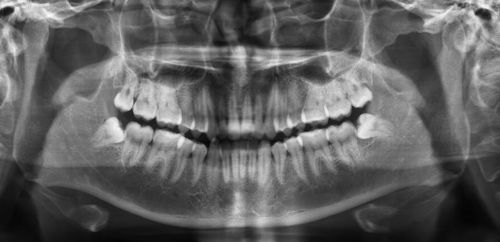

智齿可能引发的问题 智齿是否引起口腔问题取决于几方面因素,包括颌骨的大小和智齿的生长方式。

智齿通常不能正位萌出与前面的牙齿之间易形成食物滞留且不易清洁,可以导致龋坏、疼痛和肿胀等,也可能没有任何症状。

智牙又称智慧牙,是人18岁-22岁才开始萌出的1颗牙齿,通常在所有牙列最后方开始萌出,所以又称为第3磨牙。

还是由于食物过于精细的原因,我们现在已经不太需要智齿来帮助我们咀嚼消化食物了,即它的功能性差不多已经完全丧失了.而它生长的位置,现代人又不能提供出来,所以它就不按理出牌,动不动就长错地方顶到别的正常牙齿,或者侵犯。